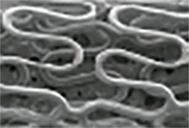

Microscopic view of stable drug coating for GuReater ™ during degradation